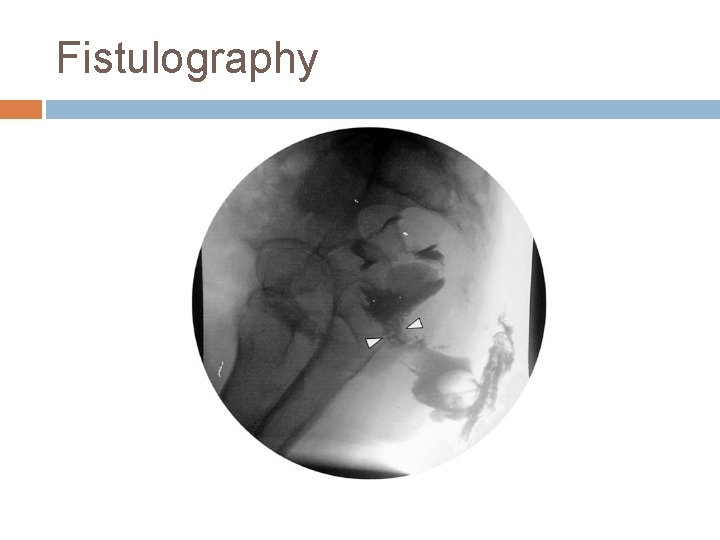

INVESTIGATION Anoscopy and sigmoidoscopy Fistulography Endoanal Ultrasonography Magnetic Resonance Imaging Endoanal Magnetic Resonance Imaging

Fistulography